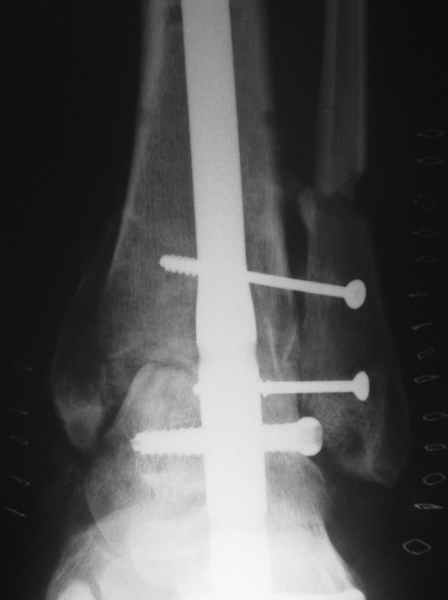

Nail arthrodesis for failed pilon fracture is good solution.

My example

Michael Berenstein

А подтаранный сустав-то за что пострадал?

А как работает подтаранный сустав после изолированного артродеза голеностопа? В литературе я не нашел убедительного ответа. По моему скромному опыту после закрытия голеностоного подтаранный болит.